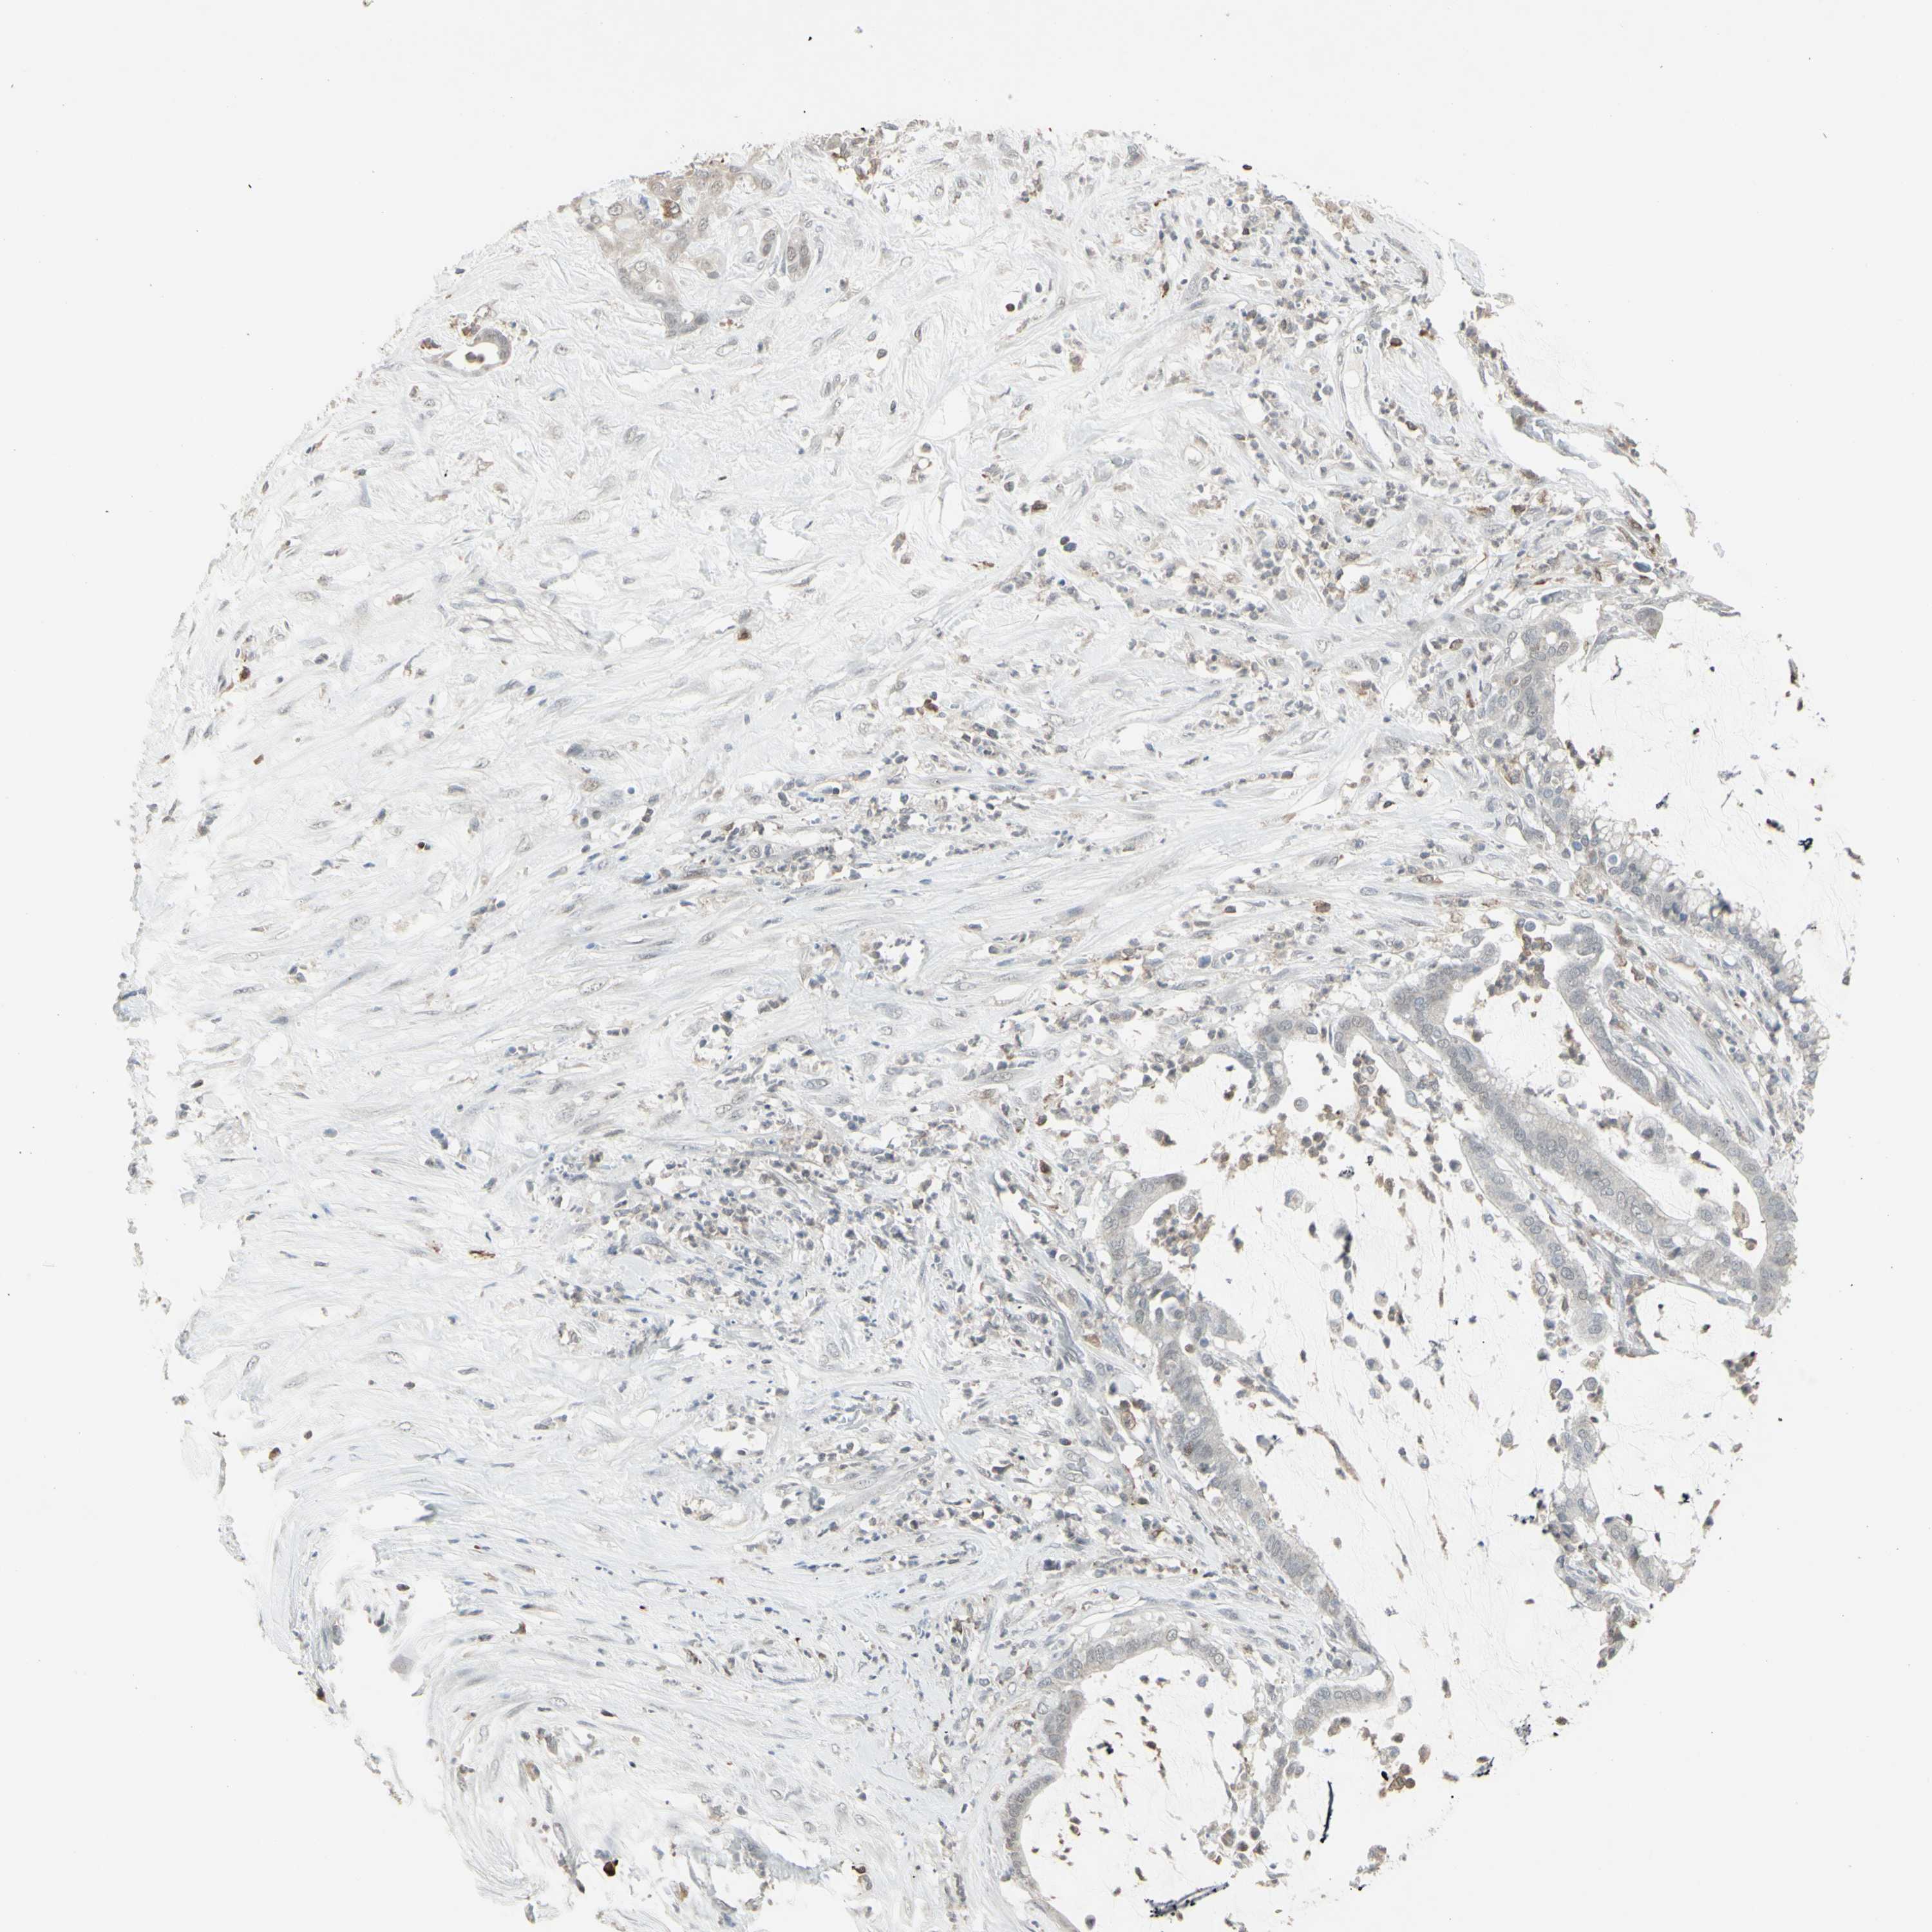

PANCREATIC CANCER - Protein expressioni

A mouse-over function shows sample information and annotation data. Click on an image to view it in a full screen mode. Samples can be filtered based on level of antibody staining by selecting one or several of the following categories: high, medium, low and not detected. The assay and annotation is described here.

Note that samples used for immunohistochemistry by the Human Protein Atlas do not correspond to samples in the TCGA dataset.

Antibody stainingi

Antibody staining in the annotated cell types in the current human tissue is reported as not detected, low, medium, or high, based on conventional immunohistochemistry profiling in selected tissues. This score is based on the combination of the staining intensity and fraction of stained cells.

Each image is clickable and will lead to virtual microscopy that enables deeper exploration of all samples and also displays staining intensity scores, fraction scores and subcellular localization as well as patient and tissue information for each sample.

Antibody HPA010645

Antibody HPA017055

Antibody HPA046639

Staining

High

Medium

Low

Not detected

Intensity

Strong

Moderate

Weak

Negative

Quantity

>75%

75%-25%

<25%

None

Location

Nuclear

Cytoplasmic/membranous

Cytoplasmic/membranous,nuclear

Adenocarcinoma, NOS

Adenocarcinoma, metastatic, NOS